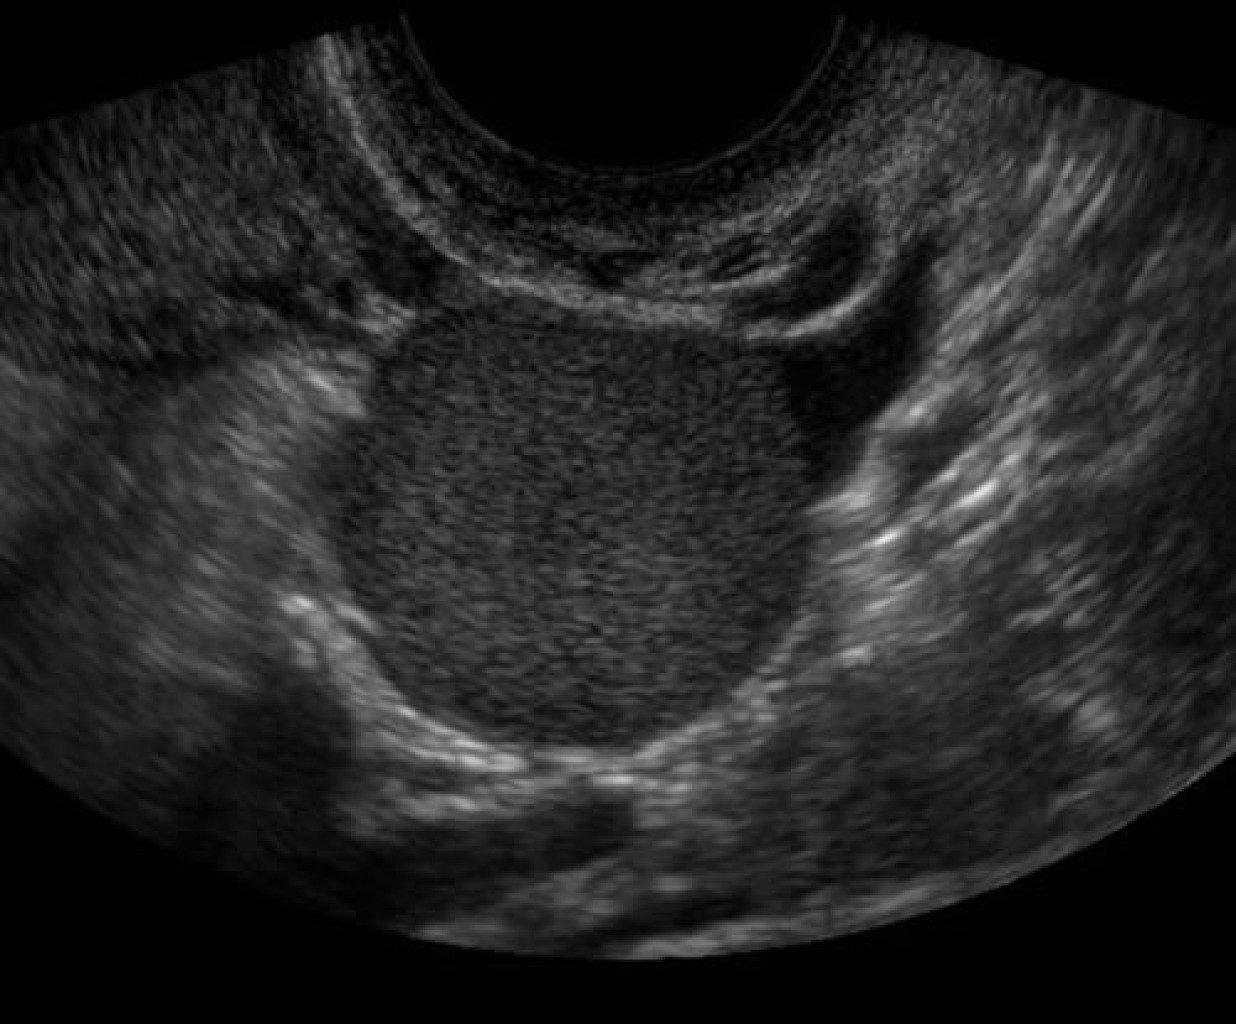

вътре в яйчника ми е кистата.Затова толкова лекари не ми я видяха,а чак репродуктивния я видя.